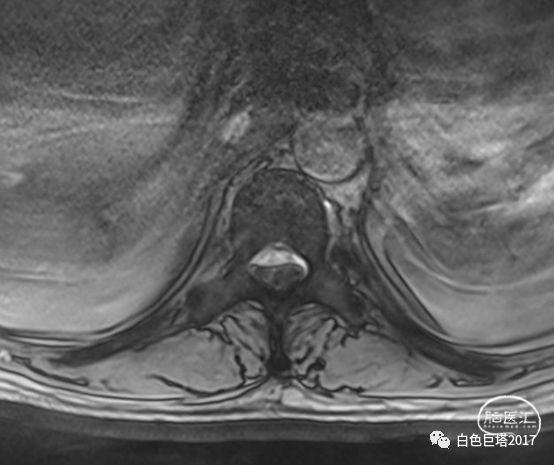

T2水平面可见相应节段脊髓明显受压。

诊断考虑1.硬脊膜外血肿(T10-12),2.症状性癫痫,3.脑出血后遗症,4.高血压3级 很高危,5.2型糖尿病,6.T8椎体血管瘤,7.右肱骨外科颈骨折固定术后,8.左肾结石,9.肝内胆管结石,10.腰椎退行性病变。

患者无外伤病史,病因可能为椎管内血管畸形如硬脊膜动静脉瘘或海绵状血管畸形,立即急诊手术挽救患者神经功能。